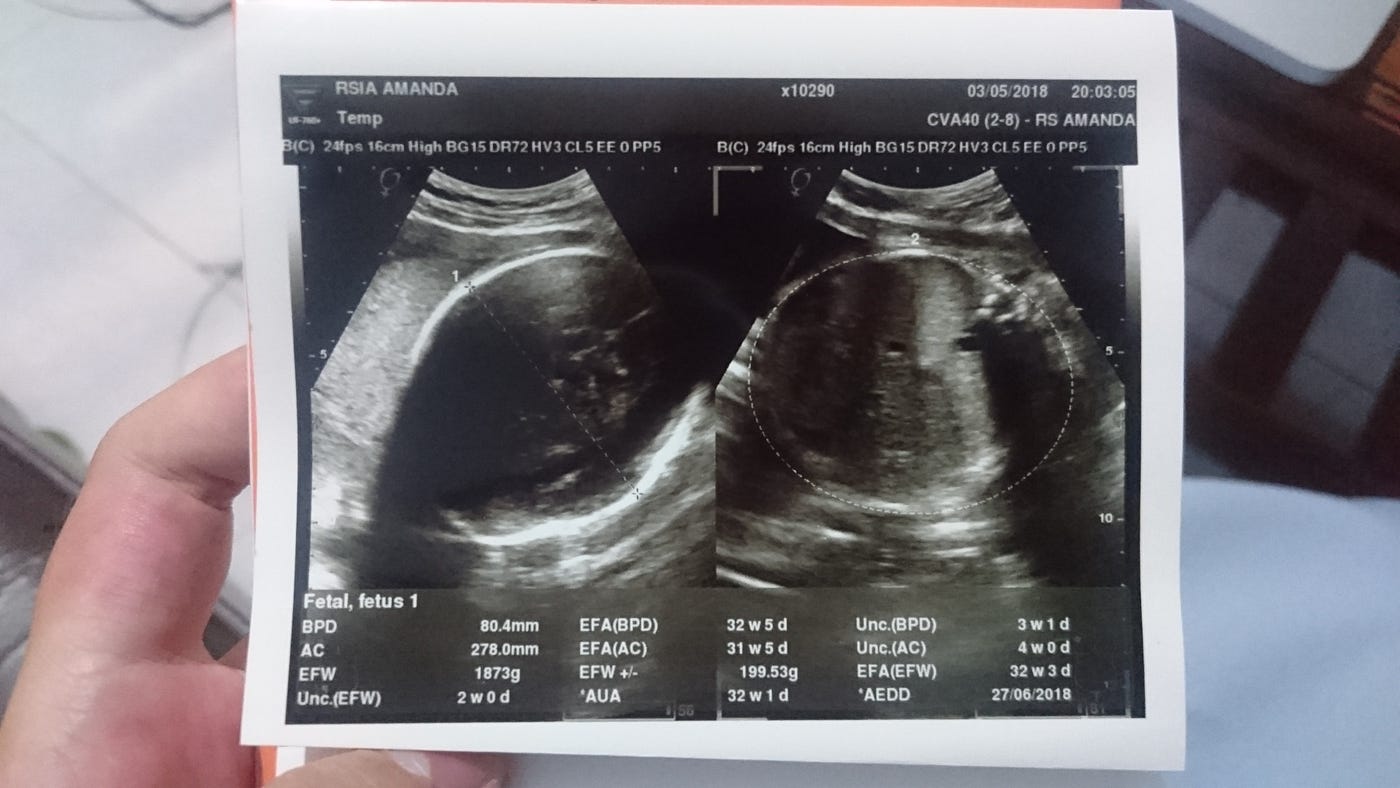

Usg program hamil umumnya meliputi 2 jenis pemeriksaan, yaitu usg transvaginal dan usg panggul. Seringkali sehabis periksa, ibu mendapat print hasil usg, tapi kesulitan dalam membaca tulisan atau gambar yang ada di hasil print tersebut. Anda hanya perlu memperhatikan dua indikator penting pada foto hasil usg, yakni warna dan orientasi gambar. Indikator warna hitam menunjukkan cairan ketuban. 5 menit membaca oleh vera khairifah pada november 23, 2020.

Di hasil usg hanya ada keterangan bpd: Usg 3d, fitur wajah janin bisa terlihat cukup jelas usg 3d dengan hasil gambar wajah janin yang lebih jelas. Pada usg 2d, gambar yang dihasilkan tampak tidak lebih jelas dibandingkan dengan usg 3d. 5 menit membaca oleh vera khairifah pada november 23, 2020. Saat ini jenis usg 2 dimensi paling banyak digunakan di indonesia. Kini, seiring berkembangnya teknologi hasil yang didapatkan semakin maksimal berupa dimensi gambar utuh (3d) bahkan bergerak (4d). Usg juga dibagi menjadi usg 2d, usg 3d dan usg 4d, fungsinya serupa, yang membedakan adalah gambar yang dihasilkan. Banyak yang bingung ya gimana sih baca usg ?

Askum dokter,, mohon bantuannya untuk membaca hasil usg saya. Indikator warna hitam menunjukkan cairan ketuban. Usg program hamil umumnya meliputi 2 jenis pemeriksaan, yaitu usg transvaginal dan usg panggul. Tampilan gambar dan data bisa dipahami dengan mudah kok, begini penjelasannya. Usg 3d ini membantu dokter mengetahui kemungkinan adanya kelainan pada janin seperti bibir sumbing dan lainnya. Di hasil usg hanya ada keterangan bpd: Cara membaca hasil usg 2 dimensi seperti di atas bisa kamu lakukan, tentunya dengan petunjuk dokter. 5 menit membaca oleh vera khairifah pada november 23, 2020. Cara mudah membaca hasil usg. Seringkali sehabis periksa, ibu mendapat print hasil usg, tapi kesulitan dalam membaca tulisan atau gambar yang ada di hasil print tersebut. Ultrasonografi (usg) adalah prosedur pencitraan dengan menggunakan gelombang suara berfrekuensi tinggi untuk menghasilkan gambar kondisi bagian dalam tubuh pasien. Sama seperti usg 2 dimensi, usg 3 dimensi menggunakan gelombang suara berfrekuensi tinggi dan peranti lunak (software) khusus untuk menangkap gambar. Pada usg 2d, gambar yang dihasilkan tampak tidak lebih jelas dibandingkan dengan usg 3d.

Berikut beberapa contoh gambar 2 dimensi: 3d (3 dimensi) sejatinya, scanning 3 dimensi yang menggunakan ultrasound pada janin menggunakan teknik gelombang suara yang sama persis dengan scanning 2 dimensi untuk menghasilkan. Agar tidak salah dalam membaca hasil usg, untuk istilah yang tertera pada usg, berikut penjelasannya ma: Bagaimana cara membaca hasil usg 2d, 3d, dan 4d? Pada usg 2d, gambar yang dihasilkan tampak tidak lebih jelas dibandingkan dengan usg 3d.

Ini adalah prosedur standar, untuk menghasilkan gambar 2 dimensi. Hal ini ditujukan untuk mengetahui apakah ada masalah atau keadaan abnormal pada rahim seperti pcos, miom, endometriosis, dan lain sebagainya. Sama seperti usg 2 dimensi, usg 3 dimensi menggunakan gelombang suara berfrekuensi tinggi dan peranti lunak (software) khusus untuk menangkap gambar. Saat ini jenis usg 2 dimensi paling banyak digunakan di indonesia. Ada beberapa istilah yang tertera dalam monitor saat ibu hamil melakukan usg. Sebab di saat ini berbagai organ seperti hidung, kaki, dan mata mulai terlihat jelas. Indikator warna hitam menunjukkan cairan ketuban. Usg program hamil umumnya meliputi 2 jenis pemeriksaan, yaitu usg transvaginal dan usg panggul.